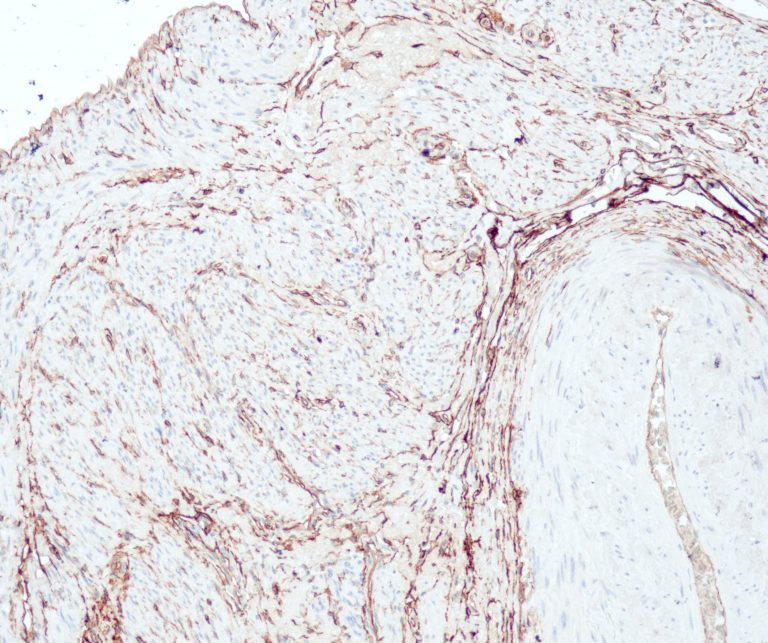

Vascular Pathology

Gastrointestinal (GI) Pathology

General Marker

Breast Pathology

Endocrine Pathology

Gynecological Pathology

Neuropathology

Infection Markers

Lung Pathology

Urinary Tract Pathology

Transplantation Pathology

Soft Tissue Pathology

Hematopathology